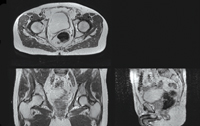

3 Automatic magnetic resonance image (MRI) segmentation results

A: Axial, coronal and sagittal views of the MRI scan of the pelvic region of one patient. |

B: Expert organ contours manually delineated from the scan in A (bones, bladder, rectum and prostate). |